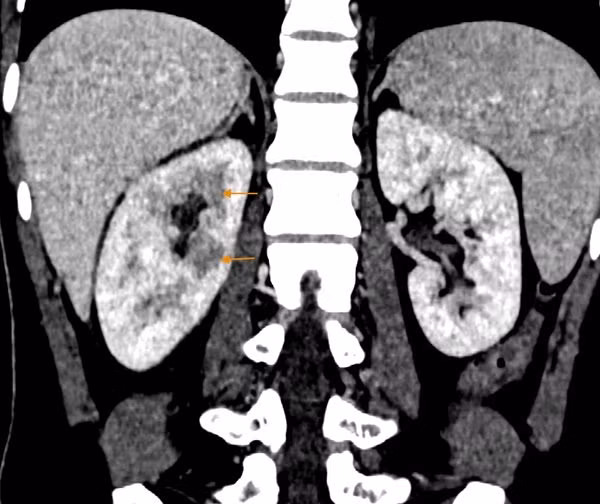

Kết quả khám lâm sàng và các xét nghiệm cần thiết cho thấy chỉ số viêm của bệnh nhân tăng, hình ảnh CT phát hiện dịch tụ quanh thận, nhu mô thận phải không đều, đặc biệt vùng sau bể thận. Bệnh nhân được chẩn đoán mắc viêm thận bể thận cấp tính, cần lập tức nhập viện điều trị nội trú.

Hình ảnh CT của bệnh nhân cho thấy nhu mô thận ngấm thuốc không đều, biểu hiện của viêm thận (Ảnh: BSCC)